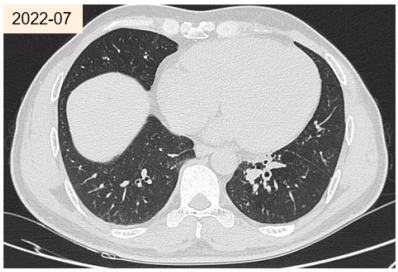

患者,男性,49岁,主因“体检发现支气管扩张3年”就诊。自诉咳褐色痰栓,外院消炎治疗后复查CT发现支气管扩张消失。否认哮喘及家族哮喘病史。居住在1楼。白细胞计数5.50×109/L,嗜酸粒细胞比值1.30%,嗜酸粒细胞绝对值0.07×109/L。

外送烟曲霉特异性IgE阴性,烟曲霉IgG阴性。痰培养提示烟曲霉。影像:指套状物,轻度支气管扩张。

abp在医学是什么意思王凌伟教授:2021日本ABPA/ABPM诊断标准解读_https://www.jmylbn.com_新闻资讯_第18张

按照日本诊断标准,ABPM待定。其他标准均无法诊断。

abp在医学是什么意思王凌伟教授:2021日本ABPA/ABPM诊断标准解读_https://www.jmylbn.com_新闻资讯_第19张